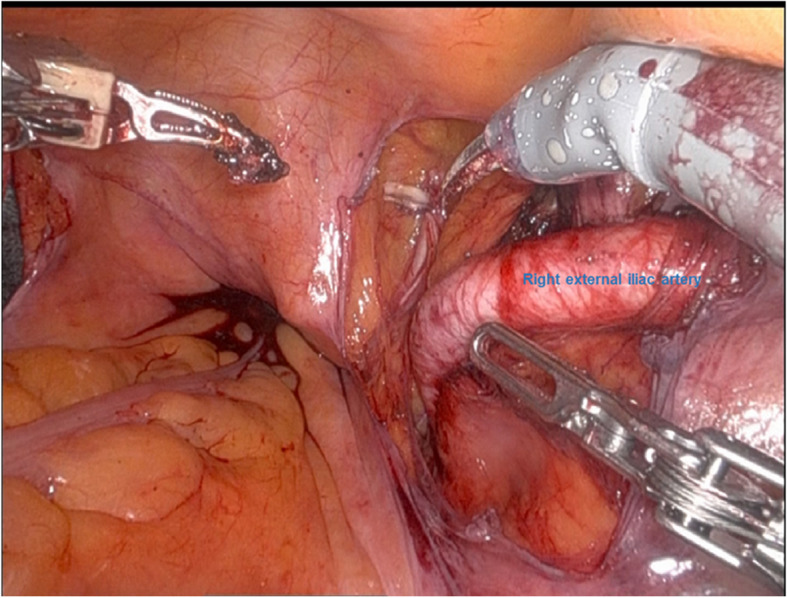

Usefulness of lower extremity pulse oximetry for detection of external iliac artery dissection during robot-assisted radical prostatectomy.